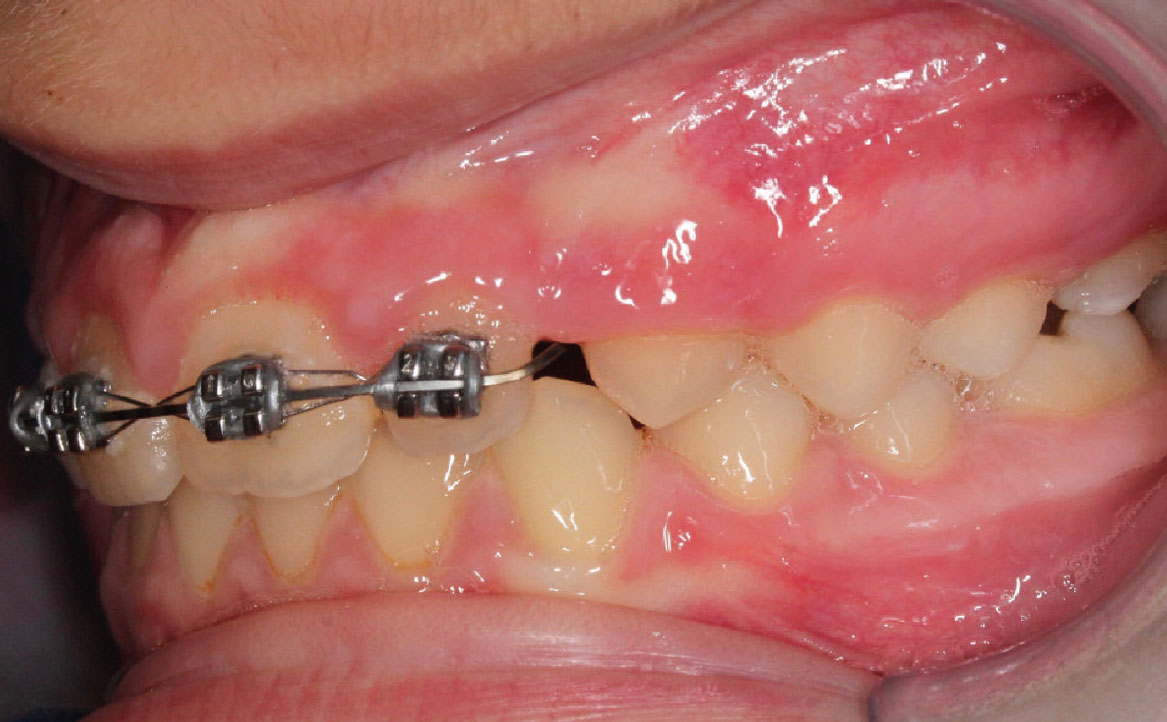

Bandaggio e sequenza archi

A tre mesi dalla cementazione dell’ERP si programma il bandaggio parziale superiore da 12 a 22 (Mini Master, prescrizione MBT, slot 22×28, American orthodontics) posizionando in maniera strategica i bk su 12 e 22, per il controllo del tip ed evitare interferenza con il tragitto eruttivo di 13 e 23. Sono state posizionate delle open coil attive e arco 016 Tanzo (fig. 8).

Fig. 8A Terapia intercettiva con REP e bandaggio parziale superiore.

Fig. 8B Terapia intercettiva con REP e bandaggio parziale superiore.

Fig. 8C Terapia intercettiva con REP e bandaggio parziale superiore.

Fig. 8E Terapia intercettiva con REP e bandaggio parziale superiore.

Fig. 8D Terapia intercettiva con REP e bandaggio parziale superiore.